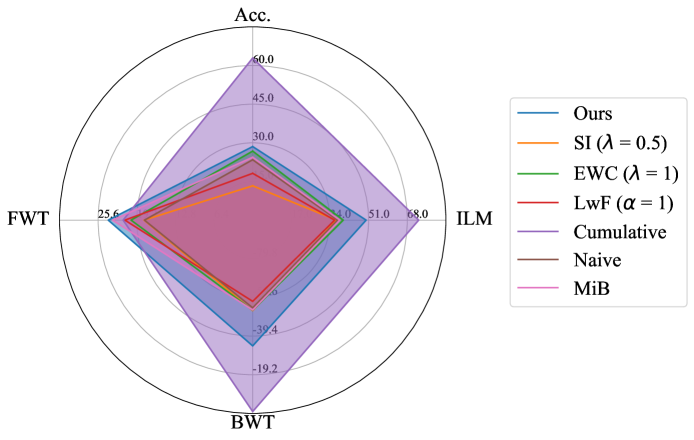

Performance comparison with others: For the considered medical applications, the primary concern will not be on improving zero-shot performance (FWT) but rather on minimizing forgetting (BWT) and enhancing the average DSC of the model (ACC and ILM). While FWT is reported for completeness, our analysis emphasize ACC, ILM, and BWT. Table 2 presents the ACC, ILM, BWT, and FWT values for all methods across sequences S1, S2, S3, and S4. Across all sequences, CL approaches (GDumb, Replay, MiB, LwF, SI, EWC, and the proposed method) mostly outperform naive training, highlighting the importance of mechanisms to mitigate catastrophic forgetting in UNet-based segmentation tasks. Further, as expected, approaches storing past data partially (Replay, GDumb) or fully (cumulative, joint training) show higher performance compared to methods (naive, MiB, LwF, SI, EWC, and the proposed approach) with no access to past exemplars. When comparing the proposed method to other buffer-free approaches (MiB, LwF, SI, EWC), it consistently achieves superior performance in all the sequences S1, S2, S3, and S4. Unlike these existing CL methods, which penalize large deviations from previously learned weights through response-level regularization terms in the training loss, the proposed approach introduces a drift-based dynamic penalization factor along with a latent-level regularization. This drift-based dual distillation allows for more effective mitigation of catastrophic forgetting. The proposed method shows a positive gain in (ACC, ILM, BWT) over best performance achieved among state-of-the art buffer-free approaches (blue colored in Table 2). Specifically, we observe an improvements of (25.51%, 9.23%, 34.34%) in S1, (6.57%, 25.28%, 31.85%) in S2, (4.85%, 11.02%, 40.15%) in S3, and (7.67%, 10.65%, 17.62%) in S4. For intuitive visualization, radar plots for S1, S2, S3, and S4, comparing cumulative, naive, the best-performing buffer-free methods, and the proposed approach are provided in Fig. 6 of Appendix.

Appendix B Radar Plot based Comparison

For intuitive visualization, Fig. 6 provides a radar plot comparing cumulative, naive, the best-performing buffer-free CL methods, and the proposed approach. In all the formulated dataset sequences, the proposed method demonstrates clear superiority over all other approaches except cumulative, which serves as the upper performance bound.